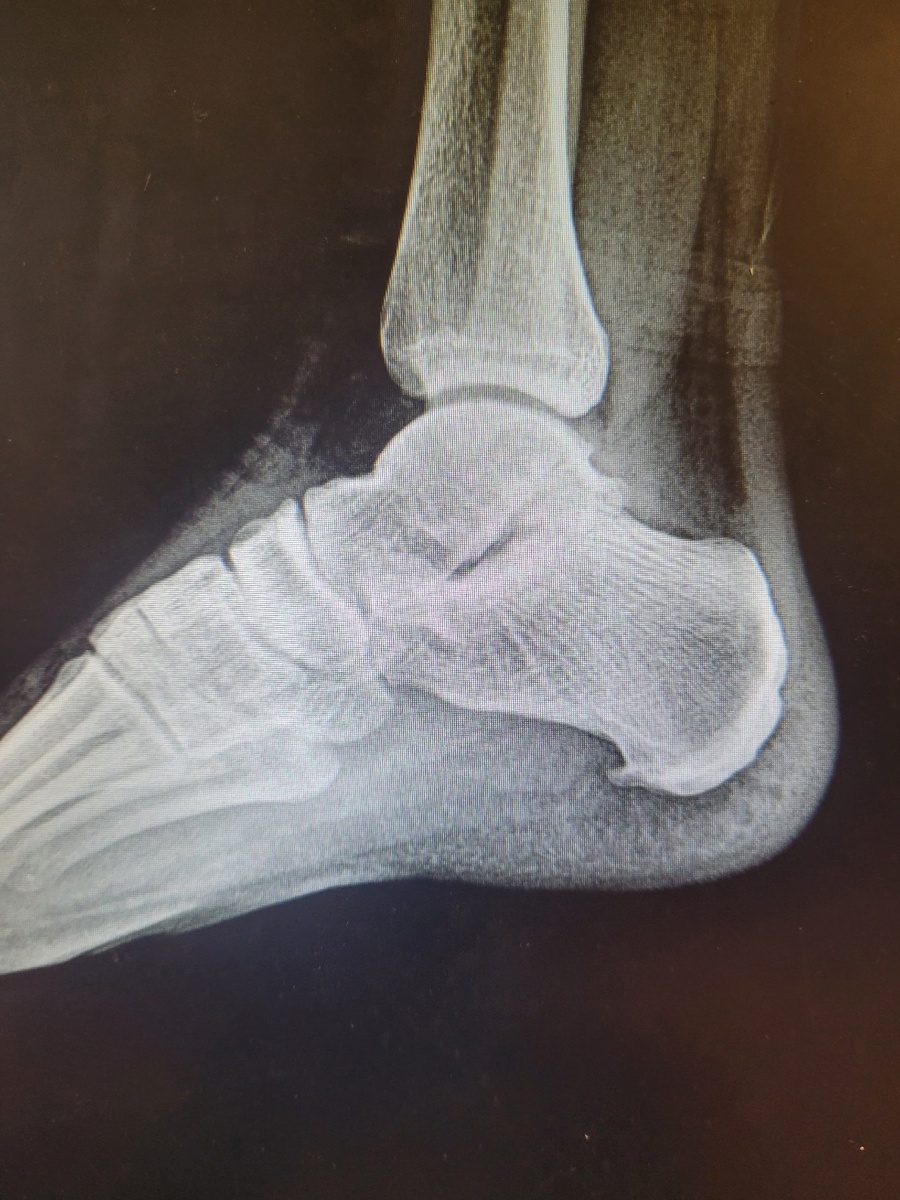

Добрый день. Подскажите пожалуйста, есть ли в Дубне хорошие конторы по изготовлению индивидуальных ортопедических стелек? Очень нужно для профилактики шпоры. Заранее спасибо!